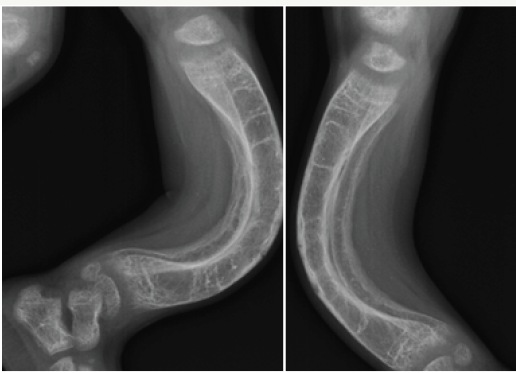

Bowing deformities and knock knees are common in the lower extremities (Figure 3a-3c).

Figure 3 c: Rickets with bowed legs

Complete healing and restoration of normal structures occurs in nutritional rickets. However distortion/sclerosis of spongiosa in affected segment may occur after healing & may remain visible for several years. Cortical thickening of segments of bone involved during active stage also may persist. Angular deformities secondary to pathological fractures result in deformities like knock-knee, bow leg and sabre shin (Figure 5).